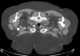

Benign symmetric lipomatosis is a skin condition characterized by extensive symmetric fat deposits in the head, neck, and shoulder girdle area. The German surgeon Otto Wilhelm Madelung was the first to give a detailed description of the disorder. [Source: Wikipedia ]

Diffuse lipomatosis of the neck

Fatty parapharyngeal space lesion

Fatty tumor of the neck